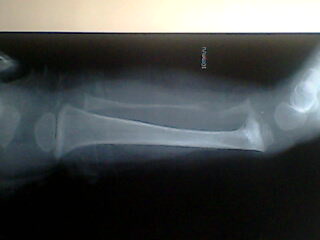

标题: PED0257:小腿

小孩腿痛波形

佝偻病

腓骨骨质溶解,大块骨质溶解症可能性大,建议进一步询问病史,进一步检查。有既往片价值更高。

左腓骨呈容骨性破坏。骨皮质及骨髓腔均破坏,下段骨不连续,周围软组织肿胀。考虑骨尤文氏肉瘤可能性大。

尤文肉瘤的明显软组织肿块与较小骨质破坏不成比例,本例似乎不符合。应考虑腓骨骨质溶解,建议询问家族史。